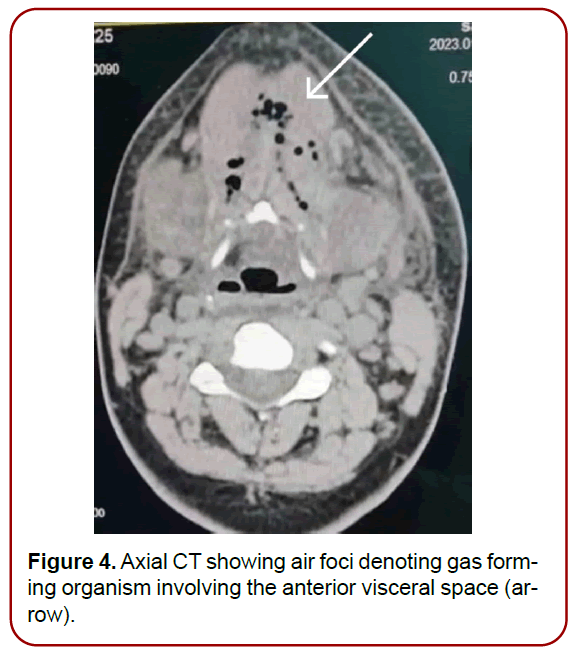

Complete blood picture showed leukocytosis. Computed tomography of the neck showed air foci in the submental, bilateral submandibular and anterior visceral neck spaces (Figure 2-4). Flexible fiberoptic assessment of the upper airway showed laryngeal edema.

Figure 4. Axial CT showing air foci denoting gas forming organism involving the anterior visceral space (arrow).